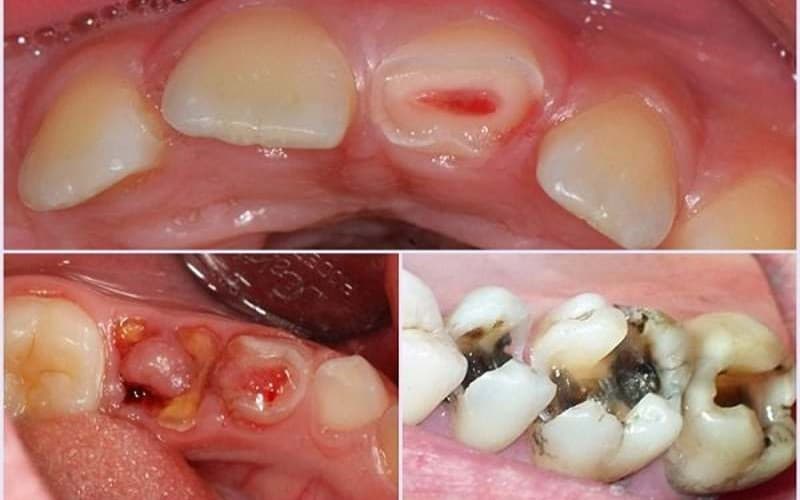

2. Răng sâu bị lồi thịt có gây nguy hiểm không?

Răng sâu lồi thịt không điều trị kịp thời có thể gây nhiều biến chứng

Răng sâu bị lồi thịt có thể gây ra nhiều vấn đề và tiềm ẩn nguy hiểm cho sức khỏe của răng và nướu. Cụ thể:

– Viêm nhiễm, đau nhức: Khi răng sâu bị lồi thịt, vi khuẩn có thể xâm nhập vào thịt nướu, gây ra viêm nhiễm và sưng đau. Viêm nhiễm có thể lan rộng và ảnh hưởng đến các cấu trúc xung quanh răng.

– Sâu răng lan rộng: Nếu không được điều trị kịp thời, vết sâu trên răng có thể lan rộng và tăng cường sự suy giảm cấu trúc răng. Điều này có thể dẫn đến các vấn đề nghiêm trọng hơn như viêm nhiễm nướu, mất răng và tổn thương cho cấu trúc răng.

– Nguy cơ mất răng: Trong một số trường hợp nghiêm trọng, vi khuẩn từ vết sâu lan rộng đến các cấu trúc răng sâu hơn như nướu và xương. Tình trạng này có thể gây ra tổn thương không thể cứu chữa được và dẫn đến việc mất răng.